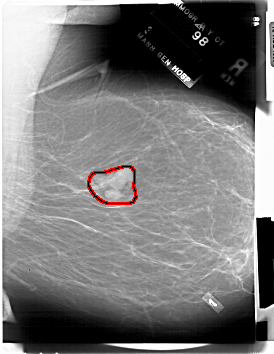

A_1843_1.RIGHT_CC

RIGHT_CC LINES 6871 PIXELS_PER_LINE 4156 BITS_PER_PIXEL 12 RESOLUTION 43.5 OVERLAY

FILE: A_1843_1.RIGHT_CC.OVERLAY

TOTAL_ABNORMALITIES 1

ABNORMALITY 1

LESION_TYPE MASS SHAPE LOBULATED MARGINS CIRCUMSCRIBED

ASSESSMENT 2

SUBTLETY 5

PATHOLOGY BENIGN

TOTAL_OUTLINES 1

BOUNDARY